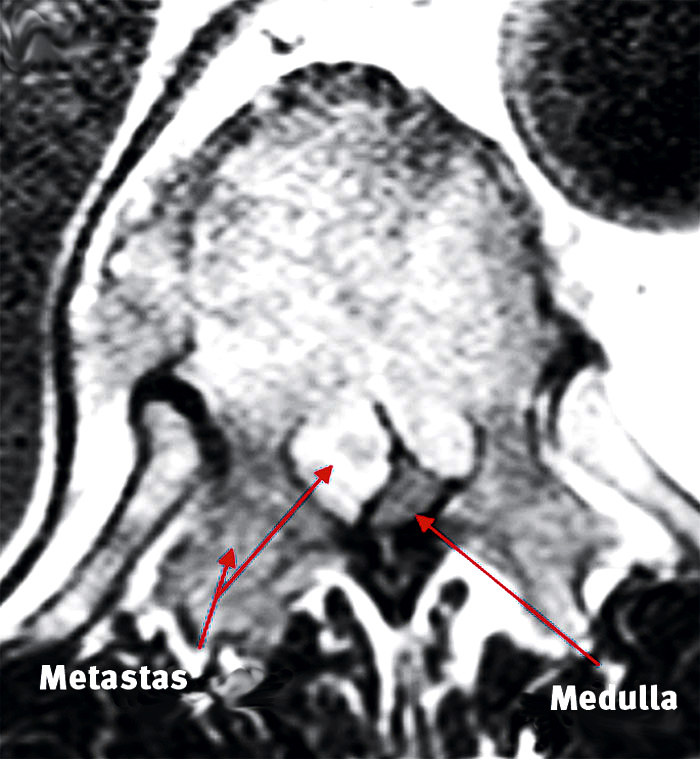

Metastatisk epidural ryggmärgskompression är en allvarlig komplikation av skelettmetastaserande tumörer och kan orsaka omfattande morbiditet inklusive paralys och påverkan på blås- och analsfinkterfunktionerna. Kompressionen uppstår antingen som följd av ett direkt tryck av en metastatisk tumörväxt eller indirekt via en destruerad eller kollapsad kota (Figur 1). Tillståndet drabbar ca 5 procent av patienterna med cancer, oftast lungcancer, prostatacancer, bröstcancer och myelom [1, 2]. Vanligtvis uppstår ryggmärgspåverkan hos patienter med kända skelettmetastaser, men ibland kan den vara den första manifestation av en tidigare okänd spridd malign sjukdom. Incidensen av metastatisk ryggmärgskompression kommer sannolikt att öka då cancerincidensen stiger på grund av en åldrande population.

Figur 1. MR-undersökning visar metastatisk ryggmärgskompression i Th 11 hos en patient med prostatacancer.